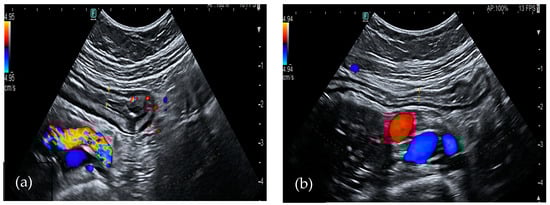

Clostridium difficile

Clostridium difficile (CD) is an anaerobic, Gram-positive, spore-forming bacillus that represents a leading cause of antibiotic-associated diarrhea. It produces two main exotoxins, toxin A and toxin B, which can harm colon epithelium and trigger an inflammatory reaction. It may lead to mucosal necrosis and the formation of pseudomembranes, which consist of an inflammatory exudate covering the exposed mucosa [49,50]. The diagnosis of the disease consists of the detection of toxins in the stool, but radiological exams also supply useful information about the infection. In particular, a CT scan is the most sensitive examination to define colon extension. In most cases, it shows pancolitis with mural thickening, even if infections limited to focal parts of the colon have also been described [51]. Moreover, a CT scan may also reveal contrast material appearing between pseudomembranes and ascites, known as the “accordion sign”. In bowel ultrasound, the wall of the large bowel appears thickened between 6 and 20 mm (Figure 2). It often shows submucosal and mucosal edema, which is represented by a heterogeneous intermediate-echogenicity band, with preservation of the muscular layer [52]. Moreover, suppurating ulcers may appear as hypoechoic defects in the hyperechoic interface between mucosa and lumen. In severe cases coalescent pseudomembranes appear as linear echogenic structures parallel to the mucosal interface [53]. Ascites is also present more commonly than in IBD, which is probably related to hypoalbuminemia and increased bowel permeability. In 2015, a case–control study compared the presence of five ultrasonographic features (colon thickness, internal and external ring, large bowel content diminution, and ascites) in patients who were hospitalized with diarrhea. The study group was toxin-positive, while the control group was toxin-negative. The colonic wall thickening was present in 91% (n = 61) of patients with CD toxin, while it was present in only 21% (n = 15) of control group. This feature had high negative and positive predictive values for Clostridium difficile infection (CDI), and the authors concluded it may help in confirming or excluding the diagnosis of CDI. Furthermore, the other ultrasound parameters had high positive predictive values and may help to confirm CDI [54]. Therefore, even if none of these findings are pathognomonic, performing bowel ultrasound is a useful tool in an acute setting, especially in patients with kidney disfunction.

Figure 2.

A 36 year-old-woman with Clostridium diarrhea. Bowel ultrasound showed colon wall thickening (a) that normalized after adequate treatment (b).